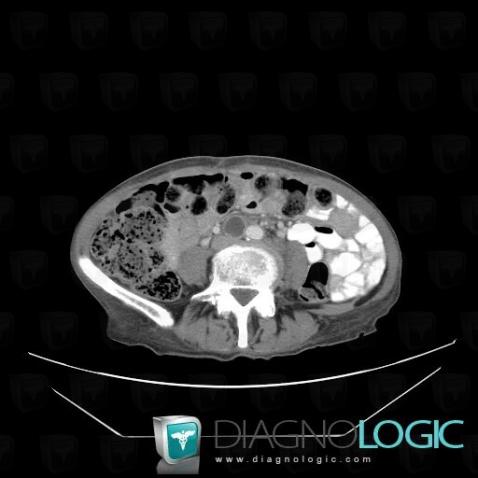

Voici les informations spécifiques à l'image clé ci dessus:

- Diagnostic Métastase (lié à Adénopathie), Localisation(s) Rétroperitoine, comportant les gammes Masse rétropéritonéale kystique

- Diagnostic Métastase, Localisation(s) Rétroperitoine, comportant les gammes Masse rétropéritonéale hypodense, Adénopathie rétropéritonéale